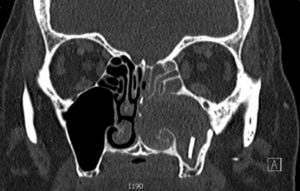

Foreign Body in Maxillary Sinus. CT Coronal. JETem 2018